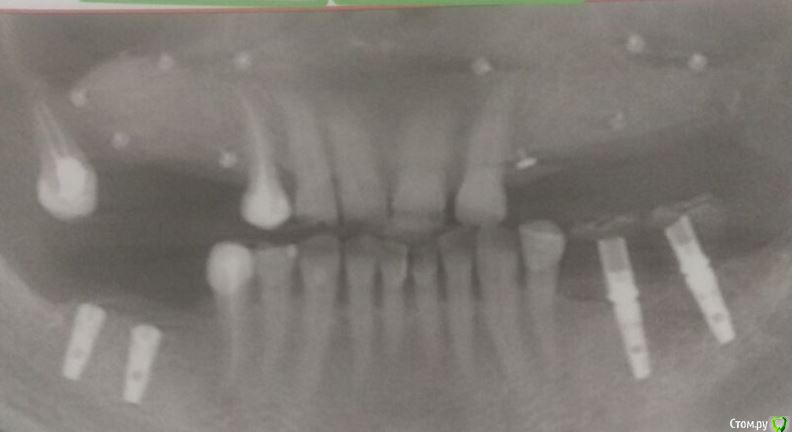

Endorphin Опубликовано 11 августа, 2015 Поделиться Опубликовано 11 августа, 2015 Добрый день, Коллеги!Хочу с Вашей помощью принять оптимальное решение по выходу из сложившейся ситуации.23.06.2015 пациентке проведена аугментация в 4 сегменте. Biooss L+ауто 50:50. Графт перекрыт мембраной biotec с титановым усилением, мембрана перекрыта отжатыми сгустками prp. Ушивание без натяжения (турбомобилизировал по Mane), матрацный и обвивной шов. 27.06 - швы состоятельны, без особенностей04.07 - снятие швов08.07 - при осмотре обратил внимание на незначительный участок оголения мембраны язычно(на фото)решил наблюдать, в надежде что затянется.Пациентка пропала на месяц.11.8.15 - Жалоб нет. Признаков воспаления нет. Обширное оголение мембраны (примерно 1 см2).Принял решение мембрану завтра удалить. Из своих косяков могу выделить слишком дистальное расположение мембраны.Причины неприятности думаю кроются в мембране - у коллеги она очень нередко ведет себя так же. На ощупь она как полиэтилен и, в отличие от cytoplast и goretex (если не ошибаюсь) не имеет пор и полностью изолирует слизистую от кости. Вопрос - как быть с дефектом мягких тканей? Из вариантов - попытаться ушить наглухо или сделать каппу (или защитную пластинку, как в кейсе Большого Зеленого) с пространством для роста грануляций. Склоняюсь ко второму варианту. Буду признателен за любые комментарии. 1 Ссылка на комментарий

Endorphin Опубликовано 9 сентября, 2015 Автор Поделиться Опубликовано 9 сентября, 2015 (изменено) Продолжение истории.По Вашим советам мембрану оставил, наблюдал пациентку раз в неделю. Отмечалась тенденция к росту области прорезывания, в связи с чем было решено мембрану удалить ( не хотелось дожидаться оголения края мембраны). На момент удаления мембране исполнилось 3 месяца. Анестезия, разрез по гребню примерно на 3/4 длины мембраны. Мембрана и пины ушли без боя, в области прорезывания обнаружился желеобразнный фибрин. Там, где над мембраной сохранилась слизистая, на месте графта образовалась твердая ткань, надо полагать, выросла кость. Иммобилизировать, ушивать наглухо, подкладывать сст не стал. Наложил сближающие швы, швы на разрез. Прошла неделя. Через 1.5 - 2 месяца планирую КТ и если это действительно была кость, то имплантацию с сст. Спасибо всем, кто отговаривал меня удалять мембрану . Изменено 9 сентября, 2015 пользователем Endorphin 13 Ссылка на комментарий

Endorphin Опубликовано 21 декабря, 2015 Автор Поделиться Опубликовано 21 декабря, 2015 Пора КТ показать. Изначально рассчитывал на большее, но на фоне осложнений, думаю, и это хороший результат. Имплантата в позиции 46 так дистально расположен именно из-за недостатка кости. В январе-феврале установка. Ссылка на комментарий